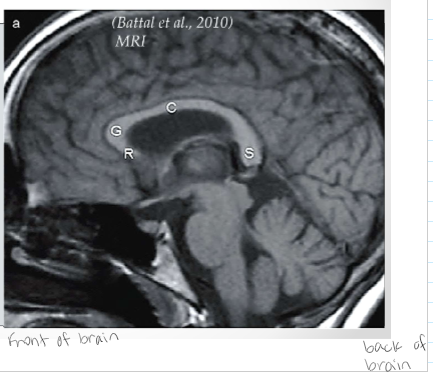

One brain structure, three different views

Spaces are lateral ventricles

Generally into 4 parts: 1. Rostrum 2. Genu 3. Corpus/Body/Trunk 4. Splenium *Be able to label them*